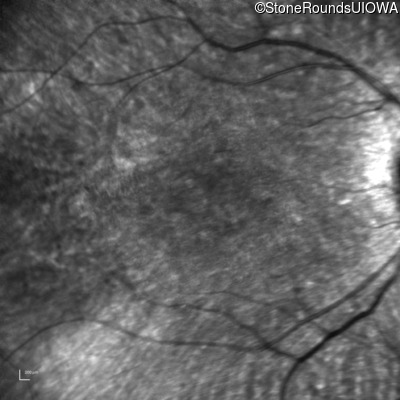

Age at visit: 10 years

Age at visit: 11 years

Age at visit: 12 years

Age at visit: 13 years

Age at visit: 14 years

Age at visit: 16 years